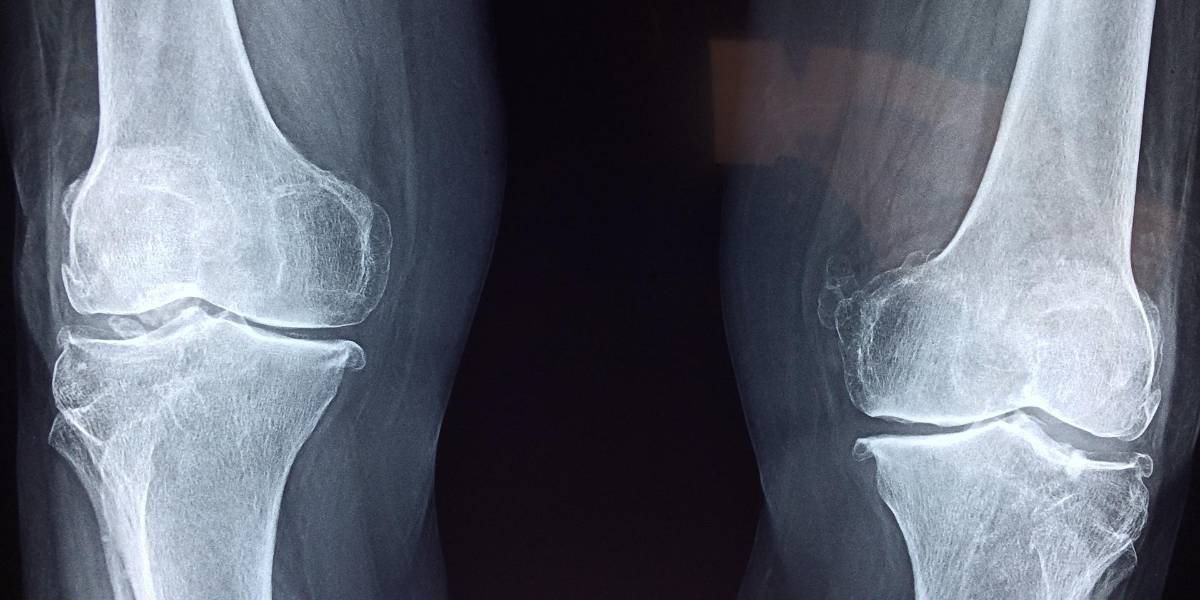

Esto provoca el infradiagnóstico de cefaleas causadas por problemas en las cervicales o en la mandíbula, lo que también dificulta identificar la solución a esos síntomas. En este sentido, los fisioterapeutas madrileños han recomendado que, ante un episodio continuado de cefalea, los pacientes consulten también con un fisioterapeuta o traumatólogo para contar con un diagnóstico más completo que permita averiguar si existe alguna patología relacionada con los huesos que pueda ser la causa o un agravante del problema.

Un dolor de cabeza causado por afecciones cervicales o mandibulares puede producir síntomas similares a la migraña, con o sin aura, y a la cefalea tensional, e incluso pueden coexistir ambos problemas y ser abordados solamente con medicación. Si eso ocurre, se estará tratando de manera no exitosa.

De ahí la importancia de contar con una valoración adicional a la neurológica y, sobre todo, de pautar un tratamiento que también tenga en cuenta, a través de la fisioterapia, la necesaria mejora de los problemas cervicales o relacionados con huesos y articulaciones involucrados en el problema. "La fisioterapia, además, puede ayudar a mejorar la higiene postural y a prevenir, con ello, episodios futuros de cefaleas, por lo que se recomienda incorporar un enfoque terapéutico al tratar el dolor de cabeza", han zanjado.